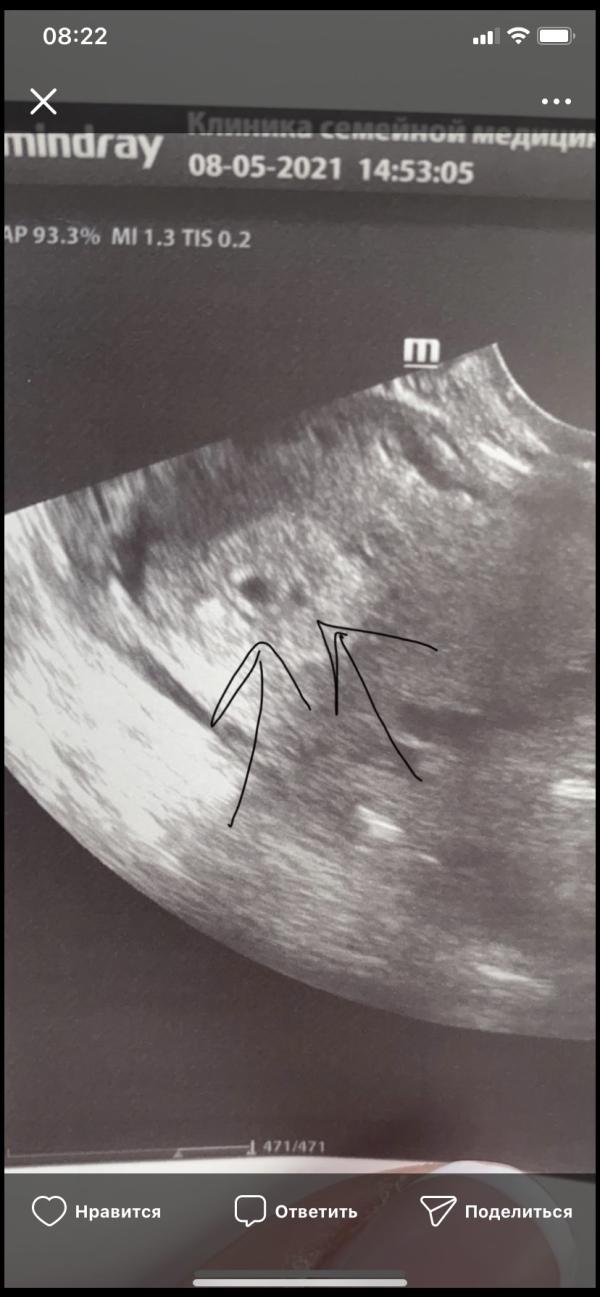

Повторили узи опять два яйца🙈

Первое фото 5 недель

Второе 4.5

Покидайте свои узи на ранних сроках 🙏

(Спросила у узиста про второе яйцо ничего не сказала, сказала на контроль через 10 дней)